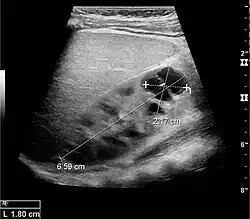

Complex cysts can have membranes dividing the fluid-filled center with internal echoes, calcifications or irregular thickened walls. The complex cyst can be further evaluated with Doppler US, and for Bosniak classification and follow-up of complex cysts, either contrast-enhanced ultrasound (CEUS) or contrast CT is used (Figure 6). The Bosniak classification is divided into four groups going from I, corresponding to a simple cyst, to IV, corresponding to a cyst with solid parts and an 85–100% risk of malignancy.[1] In polycystic kidney disease, multiple cysts of varying size in close contact with each other are seen filling virtually the entire renal region. In advanced stages of this disease, the kidneys are enlarged with a lack of corticomedullary differentiation (Figure 7).[1]

Figure 6. Complex cyst with thickened walls and membranes in the lower pole of an adult kidney. Measurements of kidney length and the complex cyst on the US image are illustrated by '+' and dashed lines.[1] -